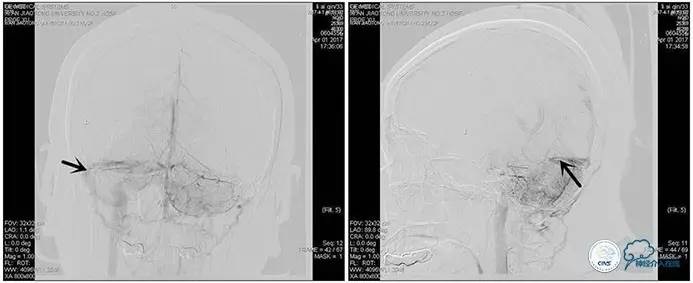

术中右侧ICA造影

右侧ICA斜位及窦内造影

右侧ICA斜位

窦内造影及路图

术中测压:

远端:520mmH2O,

近端:190mmH2O。

治疗方案:

1、8mm×40mm , EverCross球囊扩张;

2、8mm×40mm,Protégé自膨支架成形术。

术后右侧ICA造影

术后远、近端压力差为:0

术后右侧ICA斜位